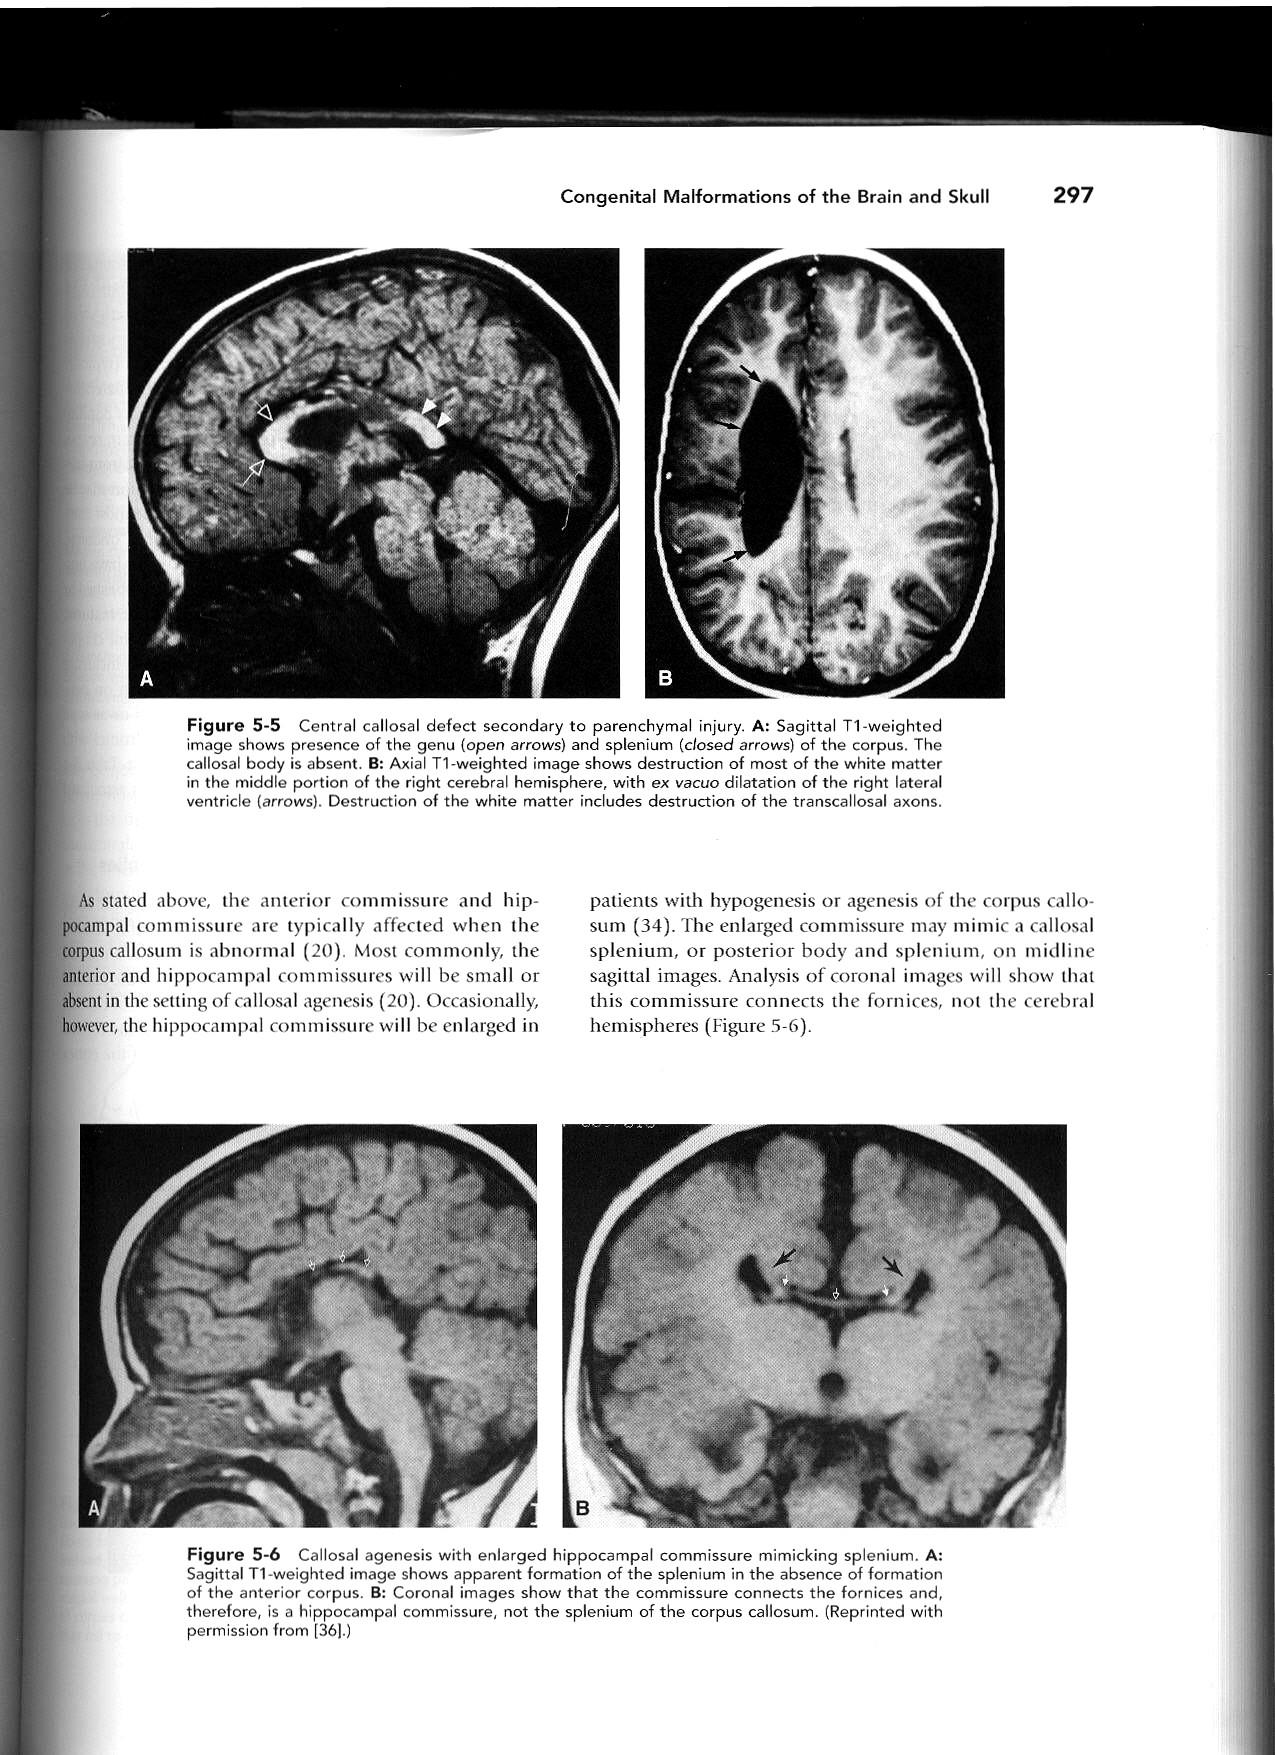

Cingulate gyrus (black arrows) “mirrors” the development of the corpus callosum.

Enlarged HC connects fornices, not cerebral hemispheres